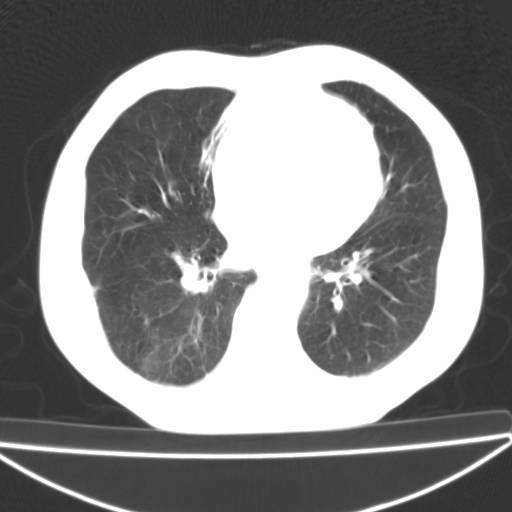

以下是引用zjzjr在2006-12-6 19:04:00的发言:[br]左肺上叶尖后段可见椭圆形高密度影,其内可见点状钙化影,周围可见卫星病灶.首先考虑结核,双侧少量胸腔积液.

以下是引用李世军在2006-12-6 19:54:00的发言:[br]左肺上叶尖后段可见椭圆形高密度影,其内可见点状钙化影,周围可见卫星病灶.首先考虑结核,双侧少量胸腔积液. [br] [br] 双肺轻度肺气肿,左肺上叶后段见多发斑片状密度增高影,周围见少许斑点状卫星病灶,双侧胸膜增厚粘连,纵隔内未见明显改变,考虑结核可能性大,请结合临床或增强扫描. [br] [br]

以下是引用13081830109在2006-12-6 19:35:00的发言:[br]左肺上叶尖后段可见椭圆形高密度影,其内可见点状钙化影,周围可见卫星病灶.首先考虑结核,双侧少量胸腔积液.

以下是引用守望可可西里在2006-12-7 0:01:00的发言:[br][quote]以下是引用zjzjr在2006-12-6 19:04:00的发言:[br]左肺上叶尖后段可见椭圆形高密度影,其内可见点状钙化影,周围可见卫星病灶.首先考虑结核,双侧少量胸腔积液.